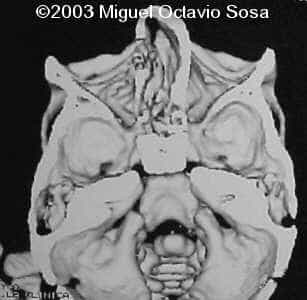

19-year-old primigravida. During third week of pregnancy, she is vaccinated with anti-measles vaccine, without knowing about the pregnancy. There are no important details before the pregnancy. These are images of the face of the fetus. Pay specific attention to the midface.

19-year-old primigravida. During third week of pregnancy, she is vaccinated with anti-measles vaccine, without knowing about the pregnancy. There are no important details before the pregnancy. At 22nd week, an ultrasound is performed demonstrating a single nasal channel on the left side and absence of right nostril.

A female newborn was delivered at 38 week, by cesarean section due to breech presentation. Size of right eye is bigger than left, and there is total absence of the right nostril. Apgar 9 at birth. No complications during postpartum. Newborn is actually under study by plastic surgeon.

These are the 3D CT reconstruction.